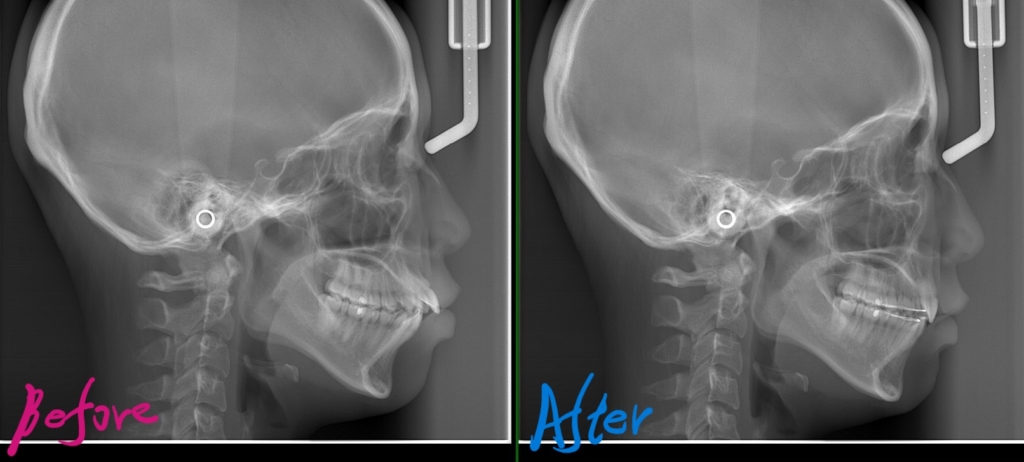

レントゲン写真でも矯正治療前後を比較してみましょう

レントゲンで見ると、治療前後で口元の変化は小さいように見えますが・・・

矯正治療前後の口元及び横顔を比較してみましょう。

上のレントゲン写真で見るよりも、顔写真で見る方が口元はスッキリして、顎もしっかりできたことが分かります

口元がスッキリして、オトガイにあった梅干し状のシワもほぼ無くなりました